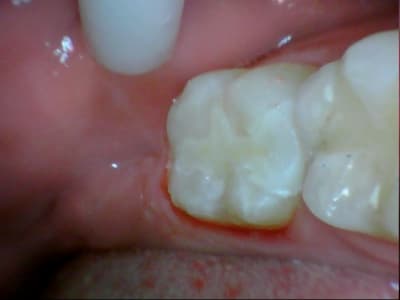

31/10/2011 à 18h09

tiens je me suis chronométré :)

28min :) lol

bon celui la etait un peu long, car provisoire collé au cvi cause durée avec le provisoire trop longue....

donc dur a déposer et obligé d'enlever les résidu de cvi aux US...

ceux qui font pas d'onlay vous proposez quoi là ?

patiente de 13 ans ...

Ca ressemble à un beau MIH avec un confrère qui a fait des trucs bizarres avec un amalgame.

Oui MIH déjà avec une belle récidive de carie. Je pense que dans un cas comme ça le compo est voué très vite à l’Échec...